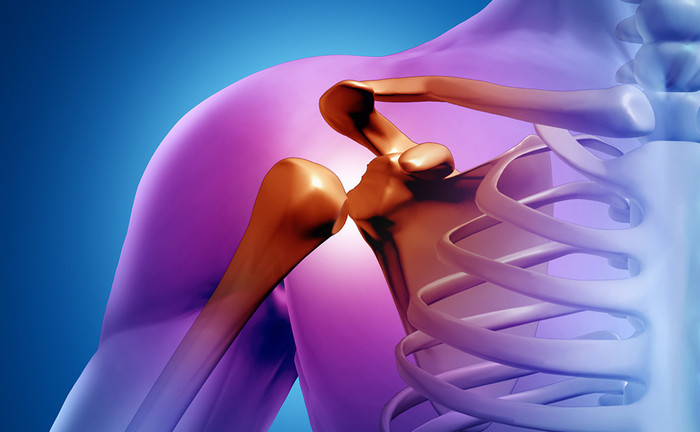

평상시 잘 사용하지 않던 몸을 사납게 사용하는 경우, 작은 바깥쪽 충격에도 뼈가 부러지는 등 골절을 겪기 쉬운 상태가 되요. 골절은 아무리 미세하고 약한 정도라도, 일상생활에 부담을 주고요.